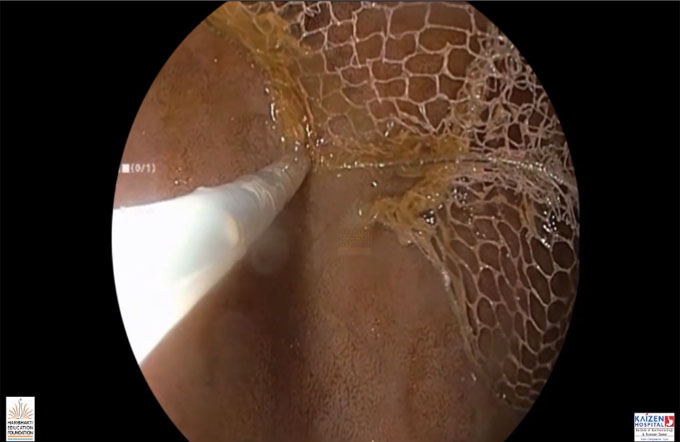

Endoscopic Necrosectomy

GI surgery Atlas